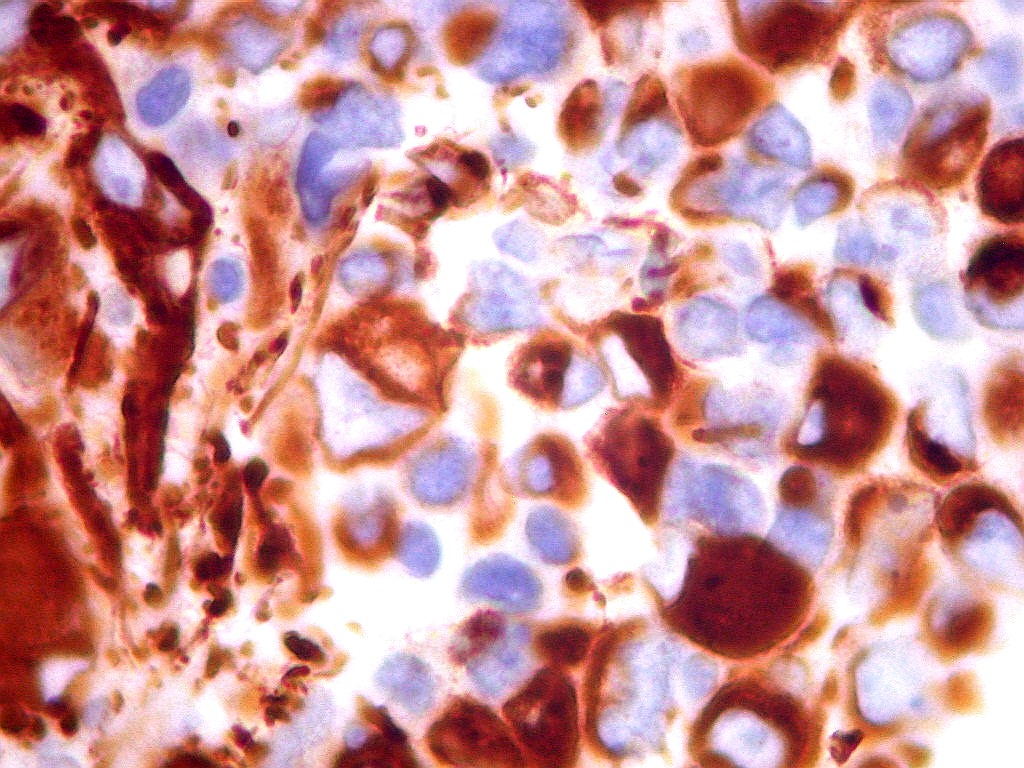

| EMA. Antígeno epitelial de membrana. Ocorre em epitélios, e também em células meningoteliais. Aqui fortemente positiva nas células deste tumor teratóide rabdóide atípico. Negativo no folículo linfóide incluído fortuitamente na amostra. Positivo também no epêndima do III ventrículo adjacente ao tumor. Notar que as células ependimárias são ciliadas. |